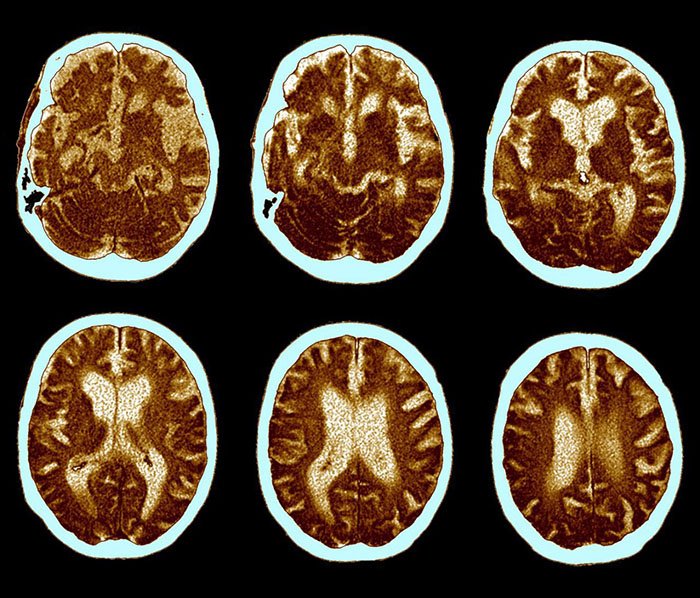

Sin embargo, este órgano, como el resto del organismo, también se deteriora, ya sea por el paso de tiempo, por una mala dieta, o simplemente, por falta de uso. Y estos factores, irremediablemente conducen a enfermedades como el Alzheimer.

La enfermedad de Alzheimer es una forma de demencia que afecta a muchas personas mayores. Una de cada cinco personas en la Tierra sufre de esta terrible enfermedad.

Por desgracia, se trata de una enfermedad degenerativa, que no tiene cura. Pero eso no significa que debemos bajar los brazos, especialmente si ya estamos cerca de la edad de jubilación.

La prevención de la enfermedad de Alzheimer se basa principalmente en una actividad mental activa. Es importante entrenar constantemente el cerebro para evitar la demencia senil.